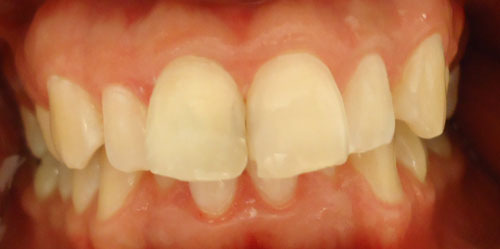

5- Segunda sesion de blanqueo interno 5 – Segunda sesion de blanqueo interno Deja un comentarioLo siento, tenés que estar conectado para publicar un comentario.